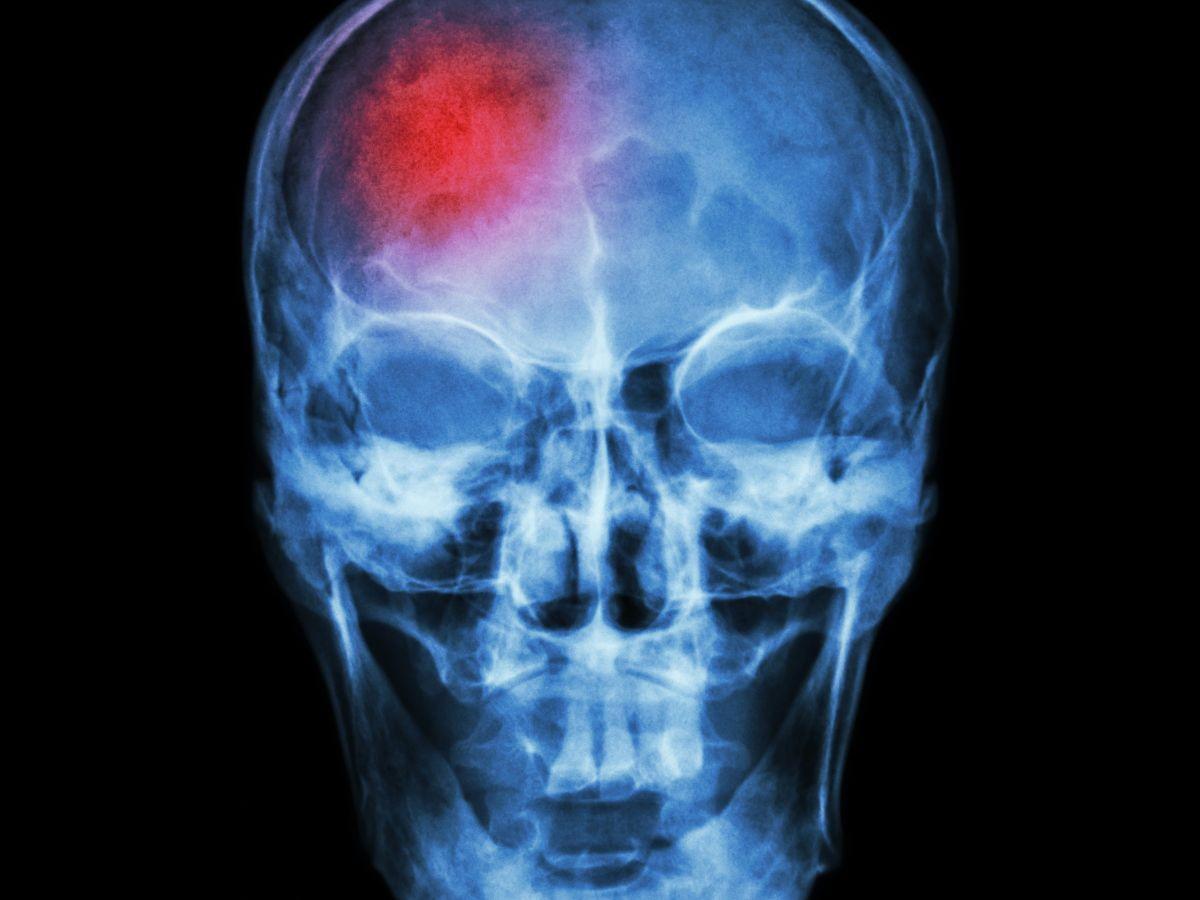

Una afección cerebrovascular es aquella en la que el flujo sanguíneo hacia el cerebro se ve comprometido en el paciente y puede desencadenarse lentamente o de manera súbita, provocando la necesidad urgente de la intervención médica, de acuerdo a especialistas de Mayo Clinic y MedlinePlus del departamento de Salud estadounidense.

Dentro de esta afección existen dos tipos de complicaciones como ser: el accidente cerebrovascular isquémico que se produce cuando el flujo sanguíneo hacia una parte del cerebro se obstruye o reduce, impidiendo que el tejido cerebral reciba oxígeno y nutrientes necesarios. Las neuronas comienzan a morir en minutos. Además, el accidente cerebrovascular hemorrágico que ocurre cuando un vaso sanguíneo en el cerebro se rompe, causando sangrado. La sangre acumulada aumenta la presión en el cerebro y daña las neuronas. En el caso particular del político hondureño no ha sido revelado la gravedad de su situación.